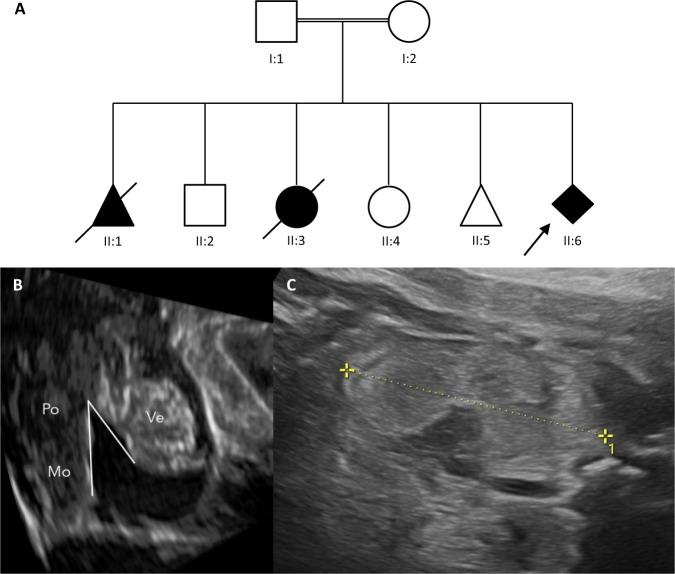

Exome sequencing has been increasingly implemented in prenatal genetic testing for fetuses with morphological abnormalities but normal rapid aneuploidy detection and microarray analysis. We present a retrospective study of 90 fetuses with different abnormal ultrasound findings, in which we employed the singleton exome sequencing (sES; 75 fetuses) or to a lesser extent (15 fetuses) a multigene panel analysis of 6713 genes as a primary tool for the detection of monogenic diseases. The detection rate of pathogenic or likely pathogenic variants in this study was 34.4%. The highest diagnostic rate of 56% was in fetuses with multiple anomalies, followed by cases with skeletal or renal abnormalities (diagnostic rate of 50%, respectively). We report 20 novel disease-causing variants in different known disease-associated genes and new genotype-phenotype associations for the genes KMT2D, MN1, CDK10, and EXOC3L2. Based on our data, we postulate that sES of fetal index cases with a concurrent sampling of parental probes for targeted testing of the origin of detected fetal variants could be a suitable tool to obtain reliable and rapid prenatal results, particularly in situations where a trio analysis is not possible.

外显子组测序已越来越多地应用于形态异常但正常快速非整倍体检测和微阵列分析的胎儿产前基因检测。我们对 90 例具有不同超声异常发现的胎儿进行了回顾性研究,其中我们使用了单胎外显子组测序(sES;75 例)或在较小程度上(15 例)使用了 6713 个基因的多基因panel 分析作为检测单基因疾病的主要工具。在这项研究中,致病性或可能致病性变异的检测率为 34.4%。最高的诊断率为 56%,见于多畸形胎儿,其次是骨骼或肾脏异常(分别为 50%的诊断率)。我们报告了 20 个不同已知疾病相关基因中的新致病变异和基因 KMT2D、MN1、CDK10 和 EXOC3L2 的新基因型-表型关联。根据我们的数据,我们假设对具有同时采集父母探针的胎儿索引病例进行 sES 靶向检测以检测检测到的胎儿变异的来源,可能是获得可靠和快速产前结果的合适工具,特别是在无法进行 trio 分析的情况下。